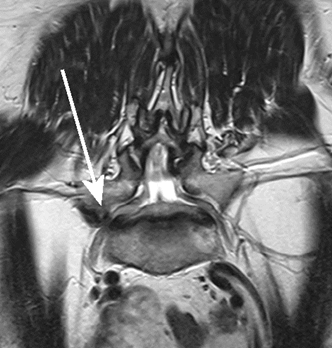

이런 경우라면 극외측 협착증이란 상태를 생각하여야 한다고 좋은아침병원 송준혁 원장은 얘기한다. 약간 생소한 이 협착증은 특수한 MRI 사진으로만 진단이 가능한 것이라 의외로 경험 많은 의료진들도 임상에서 놓치는 수가 많다고 한다.

(특수 MRI 촬영상 좌측에 비해 우측의 신경이 지나가는 부위가 좁아진 것이 명확하게 보인다)